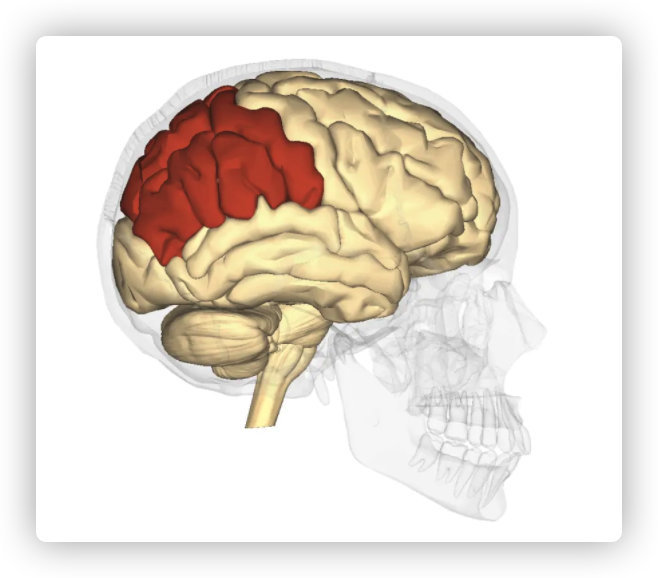

Position and anatomy of the parietal lobe

顶叶的位置和解剖

The parietal lobe is the middle part of the brain. It is located behind the central furrow towards the back. It is separated by incision preoccipitalis from the occipital lobe, lying completely posteriorly (1).

顶叶是大脑的中间部分,它位于背面中央犁沟的后面。

As already said, the parietal lobe occupies the upper side of the hemisphere. The parietal lobe limits from the anterior and lateral sides include the area from the front to the central sulcus, from the temporal floor to the lateral sulcus, from the occipital sulcus to the imaginary line that flows from the upper edge of the parietal occipital sulcus to the lower hemisphere edge.

如前所述,顶叶位于大脑半球的上半部。从前侧和外侧的顶叶界限包括从前面到中央沟、从颞底到外侧沟、从枕骨沟到从顶枕沟上缘到下半球边缘的假想线。